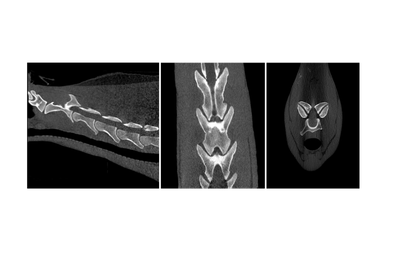

The Asto Equina is a dual-limb, fan-beam CT unit that is capable of imaging equine limbs from the carpus/tarsus down to the foot, as well as the equine head and neck. Scan acquisition is fast and able to be completed in a standing, sedated horse. This fan-beam unit captures excellent bone and soft tissue detail, allowing for diagnosis of a wide variety of pathologies.

In this presentation, Dr. Jack Caldwell of Virginia Equine Imaging (VEI) discusses how Asto CT’s standing fan-beam CT is being used in private equine practice to improve diagnostics, treatment planning, and outcomes for performance horses. Dr. Caldwell walks through real-world clinical cases involving sport horses, jumpers, dressage horses, and eventers—highlighting how standing CT has enhanced the evaluation of complex lameness, distal limb pathology, neck conditions, head trauma, and surgical planning. These cases demonstrate how CT imaging can reveal pathology that may be underestimated or missed with radiographs, ultrasound, or low-field MRI alone.